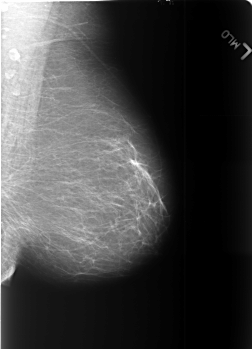

B_3451_1.LEFT_MLO

LEFT_MLO LINES 5584 PIXELS_PER_LINE 4032 BITS_PER_PIXEL 12 RESOLUTION 50 NON_OVERLAY